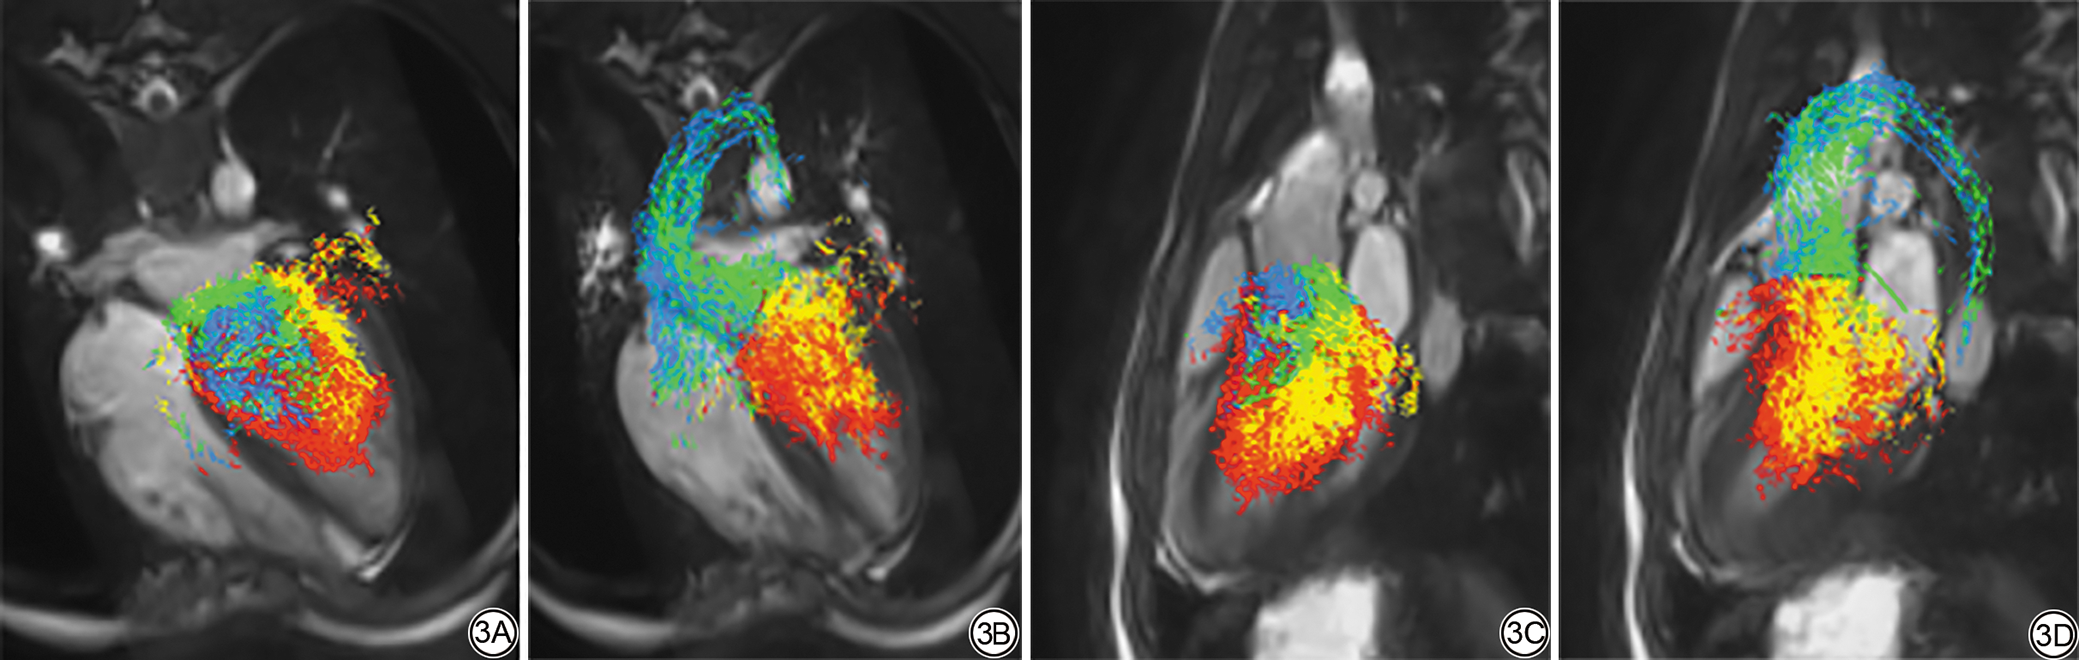

图1  血流成分示意图。心脏磁共振电影序列三腔心位。绿箭为直接血流,蓝箭为延迟射血血流,黄箭为保留流入量,红箭为剩余容积。

Fig. 1  Schematic diagram of blood flow components. Cardiac magnetic resonance cine sequence in three-chamber view. The green arrow represents direct flow, the blue arrow represents delayed ejection flow, the yellow arrow represents retained inflow, and the red arrow represents residual volume.